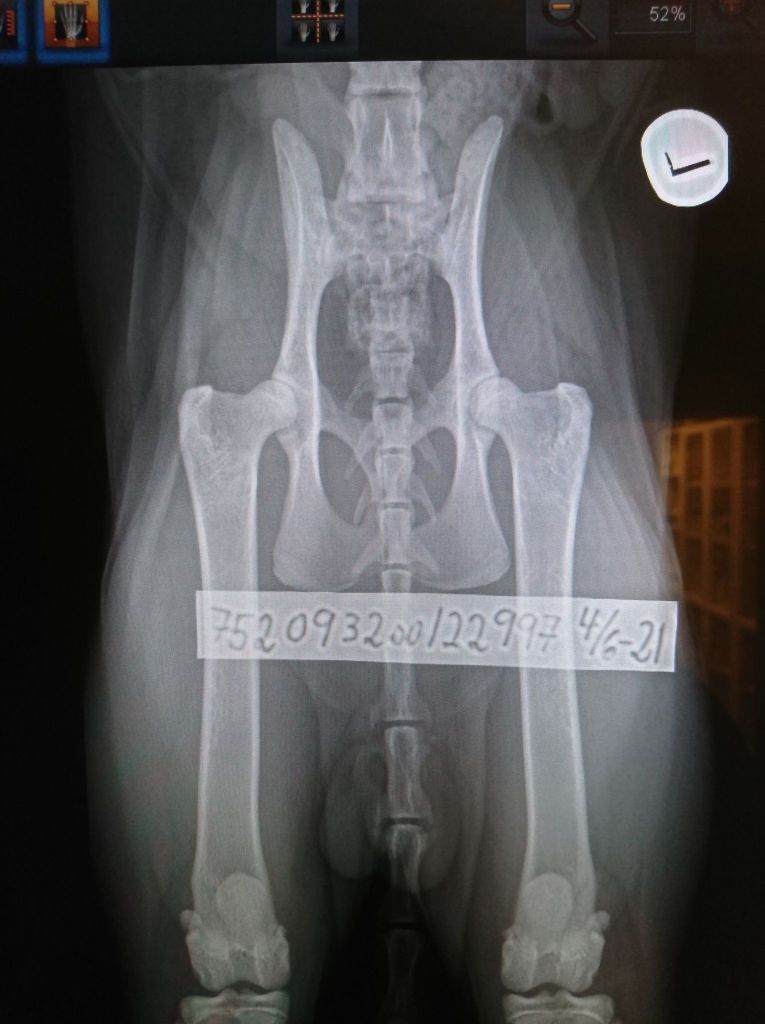

The time had come for my big boy to examine his hips. The x-ray pictures have been sent to both PawPeds and OFA for reading, mostly because I’m interested in comparing the results.

I have faith that the hips may be clear, as far as I can tell by the pictures. Nothing would have been better!